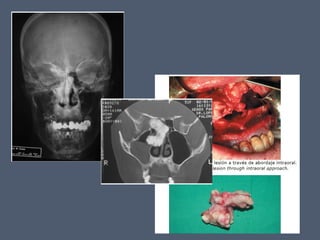

• #33 Su porc central es ósea afectado frecuentemente por fracturas faciales centrales; su por caudal distal es cartilaginosa, mas elastica y menos afetada, su porc caudal prox; est compuesta por tejido conectivo en que hay incorporado pequeños trozos de cartilago Paciente de 55 años acude a urgencias de nuestro hospital tras haber sufrido un accidente automovilístico. Se le realiza una radiografía de huesos propios en la que se visualiza claramente doble fractura de nariz.

• #41 Mujer de 51 años con obstruccion nasal de 6 meses de evolucion. osteoma nasoetmoidal acal abordaje del osteoma, que estaba anclado al etmoides por un pedículo óseo, invadía fosa nasal derecha y cerraba el orificio de drenaje del seno maxilar , tumoración a nivel etmoidal derecho que invade fosas nasales y oblitera el ostium de drenaje